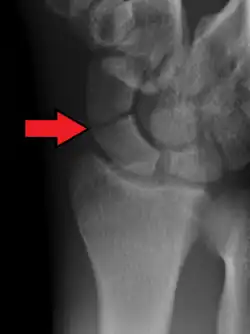

| An X-ray showing a fracture through the waist of the scaphoid | |

A scaphoid fracture is a break of the scaphoid bone in the wrist.[1] Symptoms generally includes pain at the base of the thumb which is worse with use of the hand.[2] The anatomic snuffbox is generally tender and swelling may occur.[2] Complications may include nonunion of the fracture, avascular necrosis of the proximal part of the bone, and arthritis.[2][1]